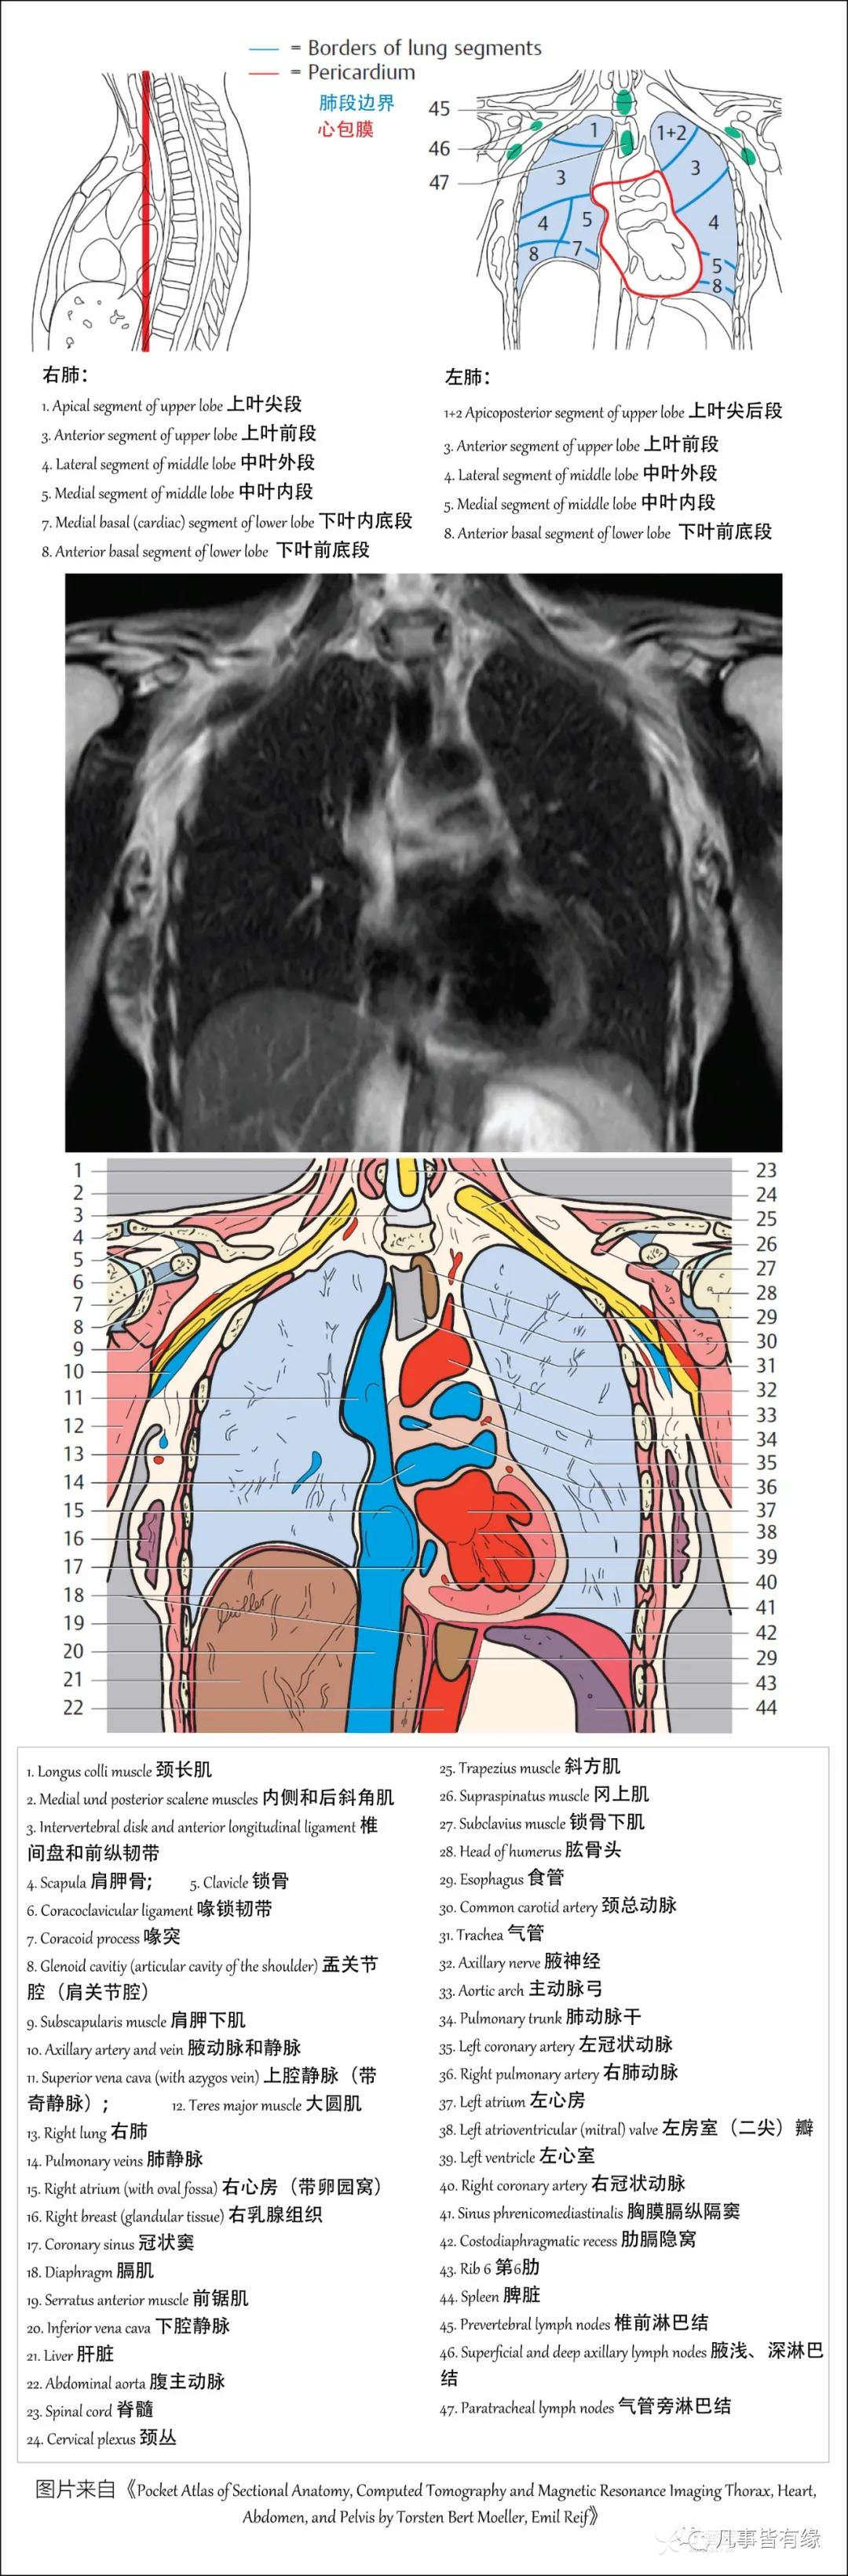

(一)胸部CT轴位断层解剖: